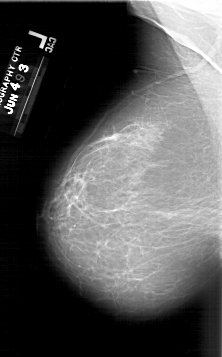

A_1640_1.LEFT_MLO

LEFT_MLO LINES 6421 PIXELS_PER_LINE 3991 BITS_PER_PIXEL 12 RESOLUTION 43.5 NON_OVERLAY